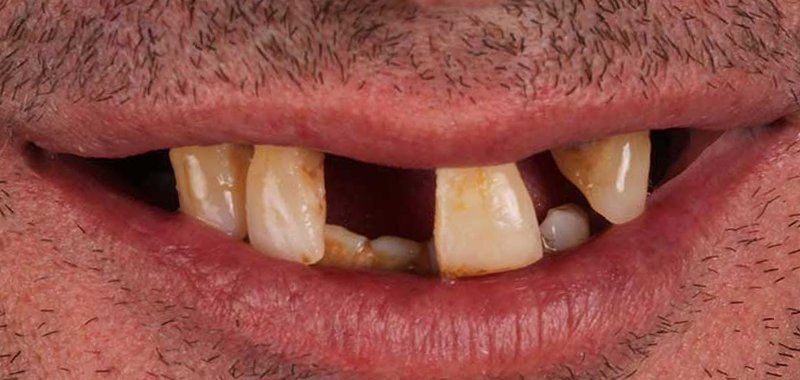

Gabino

Gabino llevaba tiempo insatisfecho con su sonrisa: tenía dientes ausentes y otros en mal estado, lo que afectaba su autoestima y bienestar. En nuestra clínica encontró la solución que buscaba: con tratamientos personalizados recuperó su sonrisa y mejoró su apariencia, ganando seguridad y confianza. Hoy disfruta de verse al espejo y mostrar al mundo una sonrisa atractiva y saludable.

Estas imágenes son testimonio de nuestro compromiso con la excelencia en la atención dental y la satisfacción del paciente. Cada sonrisa capturada aquí es el resultado de nuestro enfoque personalizado y de la utilización de las últimas tecnologías y técnicas en odontología.

Desde tratamientos de blanqueamiento dental hasta procedimientos de implantología con la tecnología X-Guide, cada paciente ha experimentado una mejora significativa en su salud dental y en su confianza en sí mismo. Pero más que palabras, creemos que una imagen vale más que mil palabras. Por eso, te invitamos a explorar estas fotos y a ver por ti mismo los resultados que puedes esperar cuando confías en la Clínica Dental Guitián.